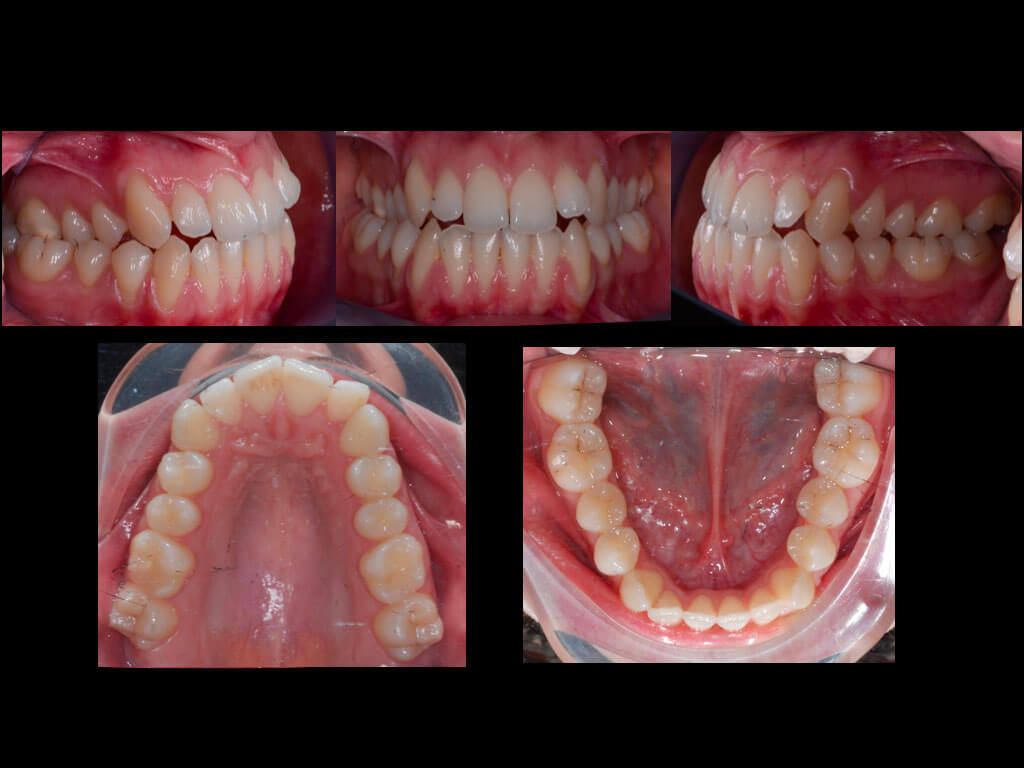

Cada alineador se utilizó durante siete días y, tras esta primera serie, se programó el acabado de otros cinco alineadores superiores e inferiores. Por lo tanto, el tratamiento global se completó en diez meses, de los que sólo seis se realizaron con alineadores F22. Clínicamente, el paciente muestra una clase 1 de relación molar y canina y diámetros transversales posteriores correctos. Las recesiones no empeoraron durante la terapia y ahora se pueden tratar con un enfoque quirúrgico de cobertura radicular.

Dopo